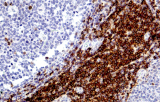

- Linfoma di Hodgkin classico: le cellule tumorali sono tipicamente CD30+ e spesso CD15+, con PAX5 debole e CD20 negativo nelle grandi cellule tumorali.